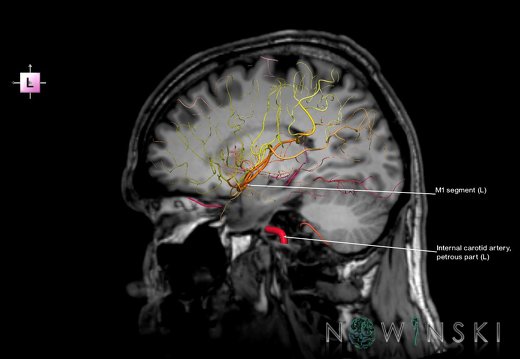

G6.T15.2.V2.P00.Intracranial arteries–Triplanar

G6.T15.2.V2.P00S.Intracranial arteries–Triplanar